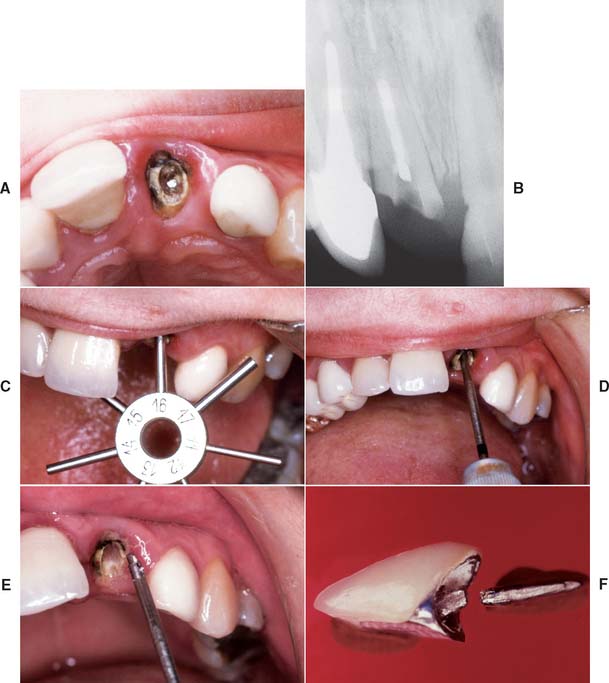

Fiber composite posts have increased in popularity. These posts consist of bundles of stretched aligned glass or carbon fibers* embedded in a resin matrix. The resulting post is strong but has significantly less stiffness and strength than do ceramic and metal posts.64 Preliminary retrospective study of the carbon fiber system appears promising65 (Fig. 12-30). However, in a laboratory study in which teeth restored with carbon fiber posts and composite-resin foundations were compared with teeth restored with custom post and cores cast in type III alloy, there were significantly higher fracture thresholds for the cast post and cores.66 One advantage of a fiber composite posts is their ease of its removal for re-treatment. The preferred technique involves drilling in an apical direction. The very strong carbon fibers prevent the drill from tracking laterally, avoiding penetration of the dentin and preventing the post from shattering easily into small fragments (Fig. 12-31).

Fig. 12-30 Fiber composite posts. A and B, The ParaPost Fiber Lux system is available in various sizes. C, Gutta-percha is removed with hot instruments or a Gates Glidden drill. The canal is prepared sequentially with the drills provided by the manufacturer. D, The post is seated in the canal. E, The canal is prepared by etching and priming according to the manufacturer’s recommendations. F, The luting resin is introduced into the canal with a paper point. G, The post is coated with resin luting agent, seated and the resin polymerized (H). The translucent post allows light transmission to the luting agent. I, The core is built up with the recommended core resin. J, The preparation is finalized.

(Courtesy of Coltène/Whaledent AG, Altstatten, Switzerland.)

Fig. 12-31 A, Maxillary canine requires fiber post removal for endodontic re-treatment B, Composite resin core is removed first. C, Gates Glidden drill used to remove the fiber post. D, Endodontically re-treated tooth before fabrication of new post and core and extracoronal restoration. If concern exists about the long-term prognosis of an endodontically treated tooth, a carbon fiber post should be considered. The chief disadvantage of a carbon fiber post is its black appearance, which presents an esthetic problem (as can metal posts).

(Courtesy Dr. D.A. Miller.)